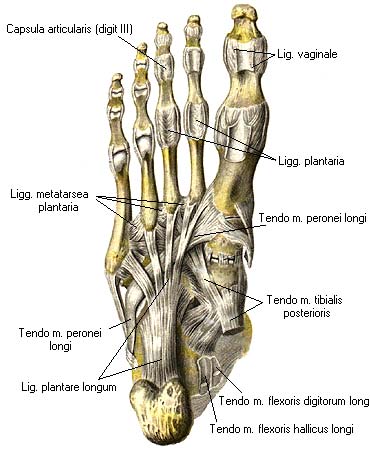

Анатомические фото голеностопного сустава и его суставных поверхностей